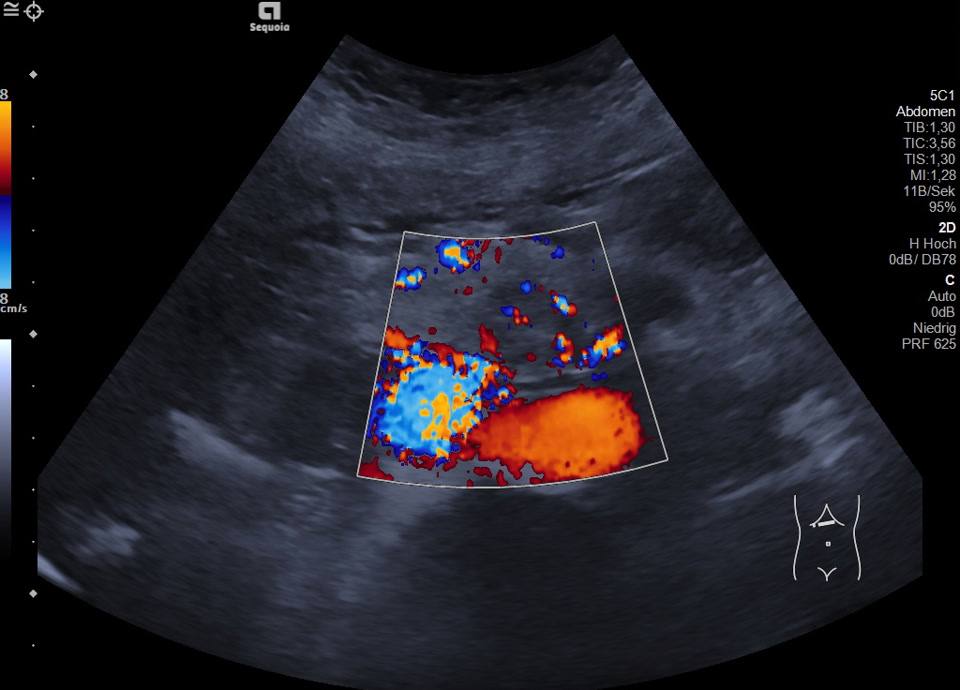

Case

60-year-old female patient with incidental finding of serous cystadenoma one year ago. Current follow-up examination reveals small cystic mass (honeycomb pattern visible on EUS) of constant size in the head of the pancreas/uncinate process. In the transcutaneous B-scan, central echogenic portion (central scar), hypervascularized on color Doppler sonography.